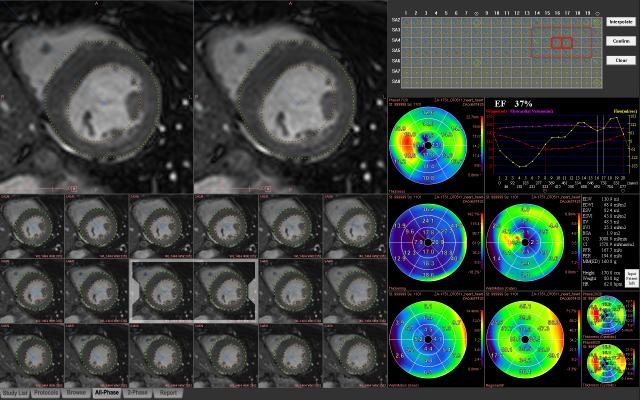

For the study, Kuetting and colleagues recruited 20 healthy radiologists, including 19 men and one woman, with a mean age of 31.6 years. Each of the study participants underwent cardiovascular magnetic resonance (CMR) imaging with strain analysis before and after a 24-hour shift with an average of three hours of sleep.

"Cardiac function in the context of sleep deprivation has not previously been investigated with CMR strain analysis, the most sensitive parameter of cardiac contractility," Kuetting said.

Following short-term sleep deprivation, the participants showed significant increases in mean peak systolic strain (pre = -21.9; post = -23.4), systolic (112.8; 118.5) and diastolic (62.9; 69.2) blood pressure and heart rate (63.0; 68.9). In addition, the participants had significant increases in levels of thyroid stimulating hormone (TSH), thyroid hormones FT3 and FT4, and cortisol, a hormone released by the body in response to stress.